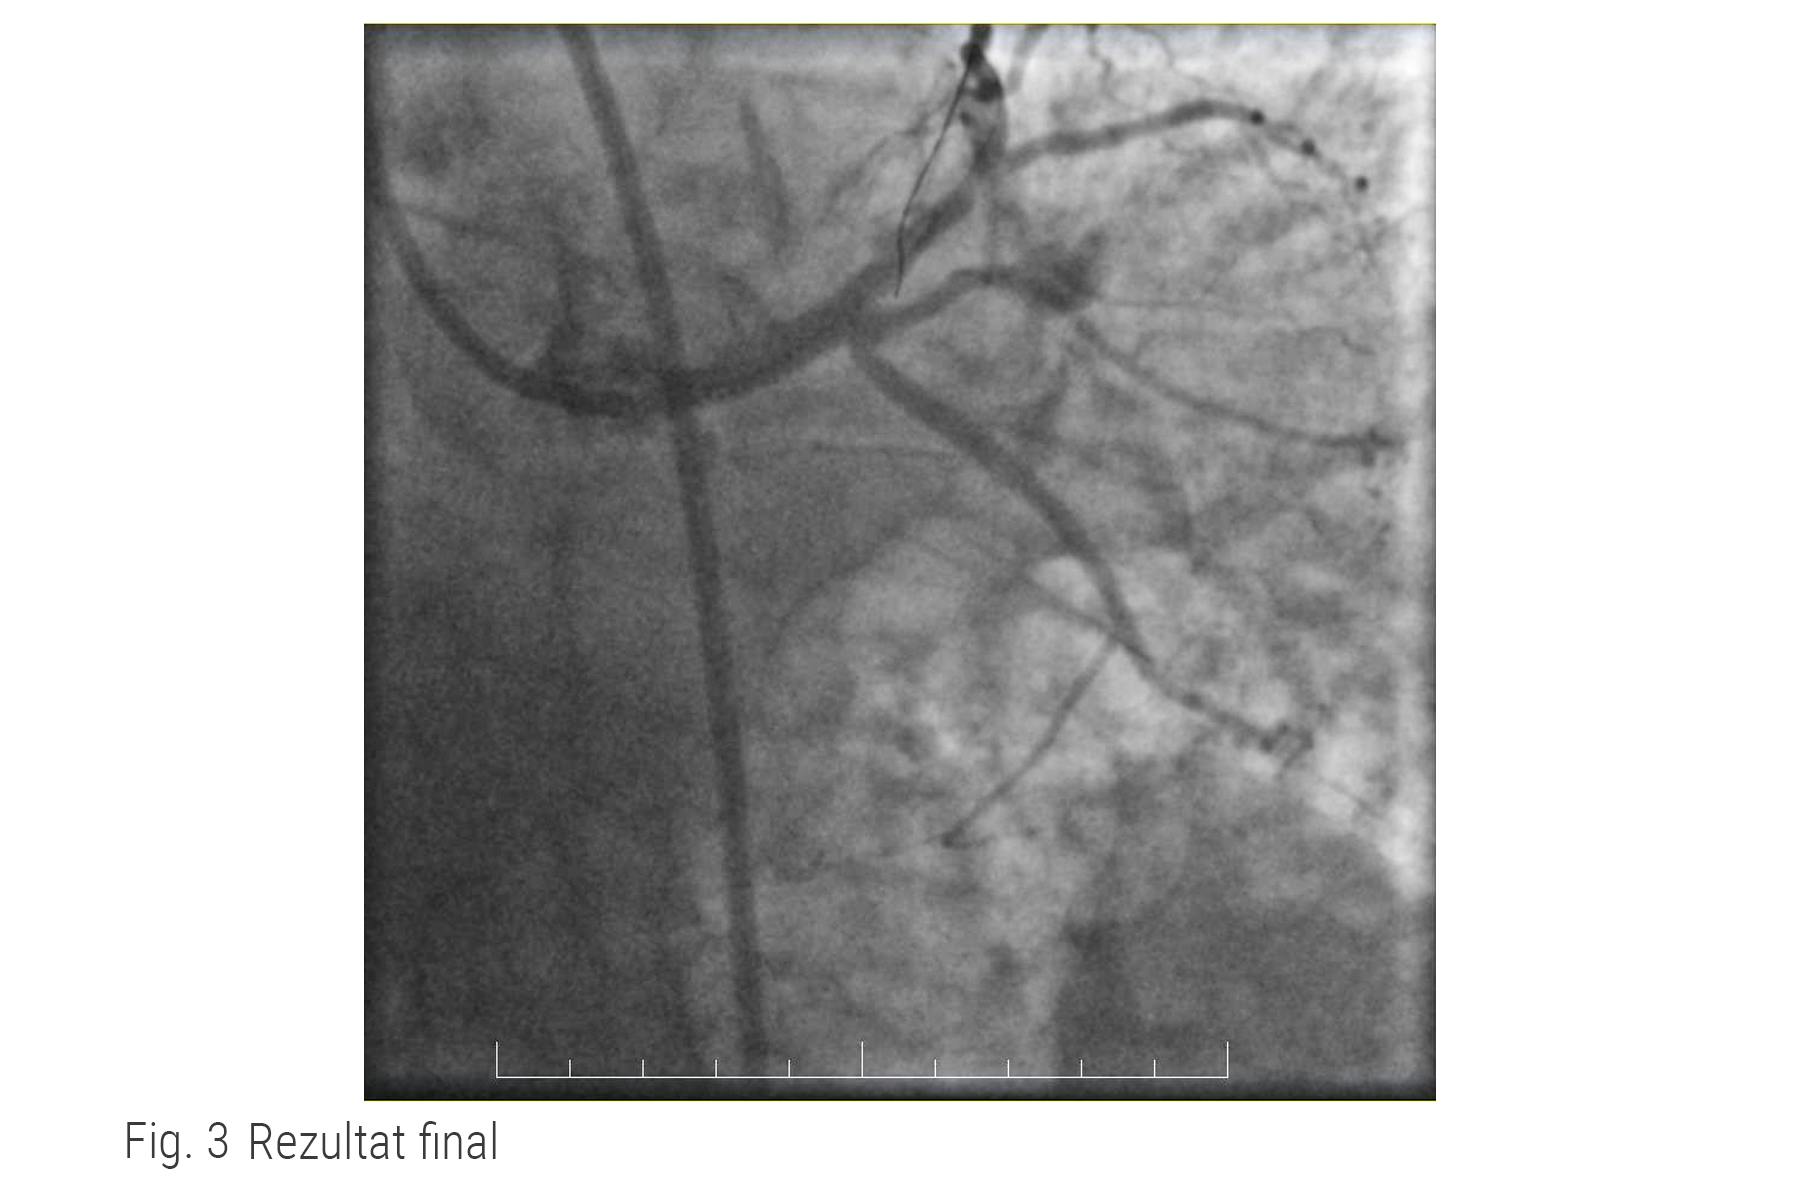

Rezultat caz ARES

În ceea ce îl privește pe pacientul nostru, acesta se află în afara oricărui pericol cardiac, rezultatul procedurii este un succes medical, iar el este externat în stare foarte bună cu mențiunea de a respecta recomandările medicale și de a reveni la controlul periodic.